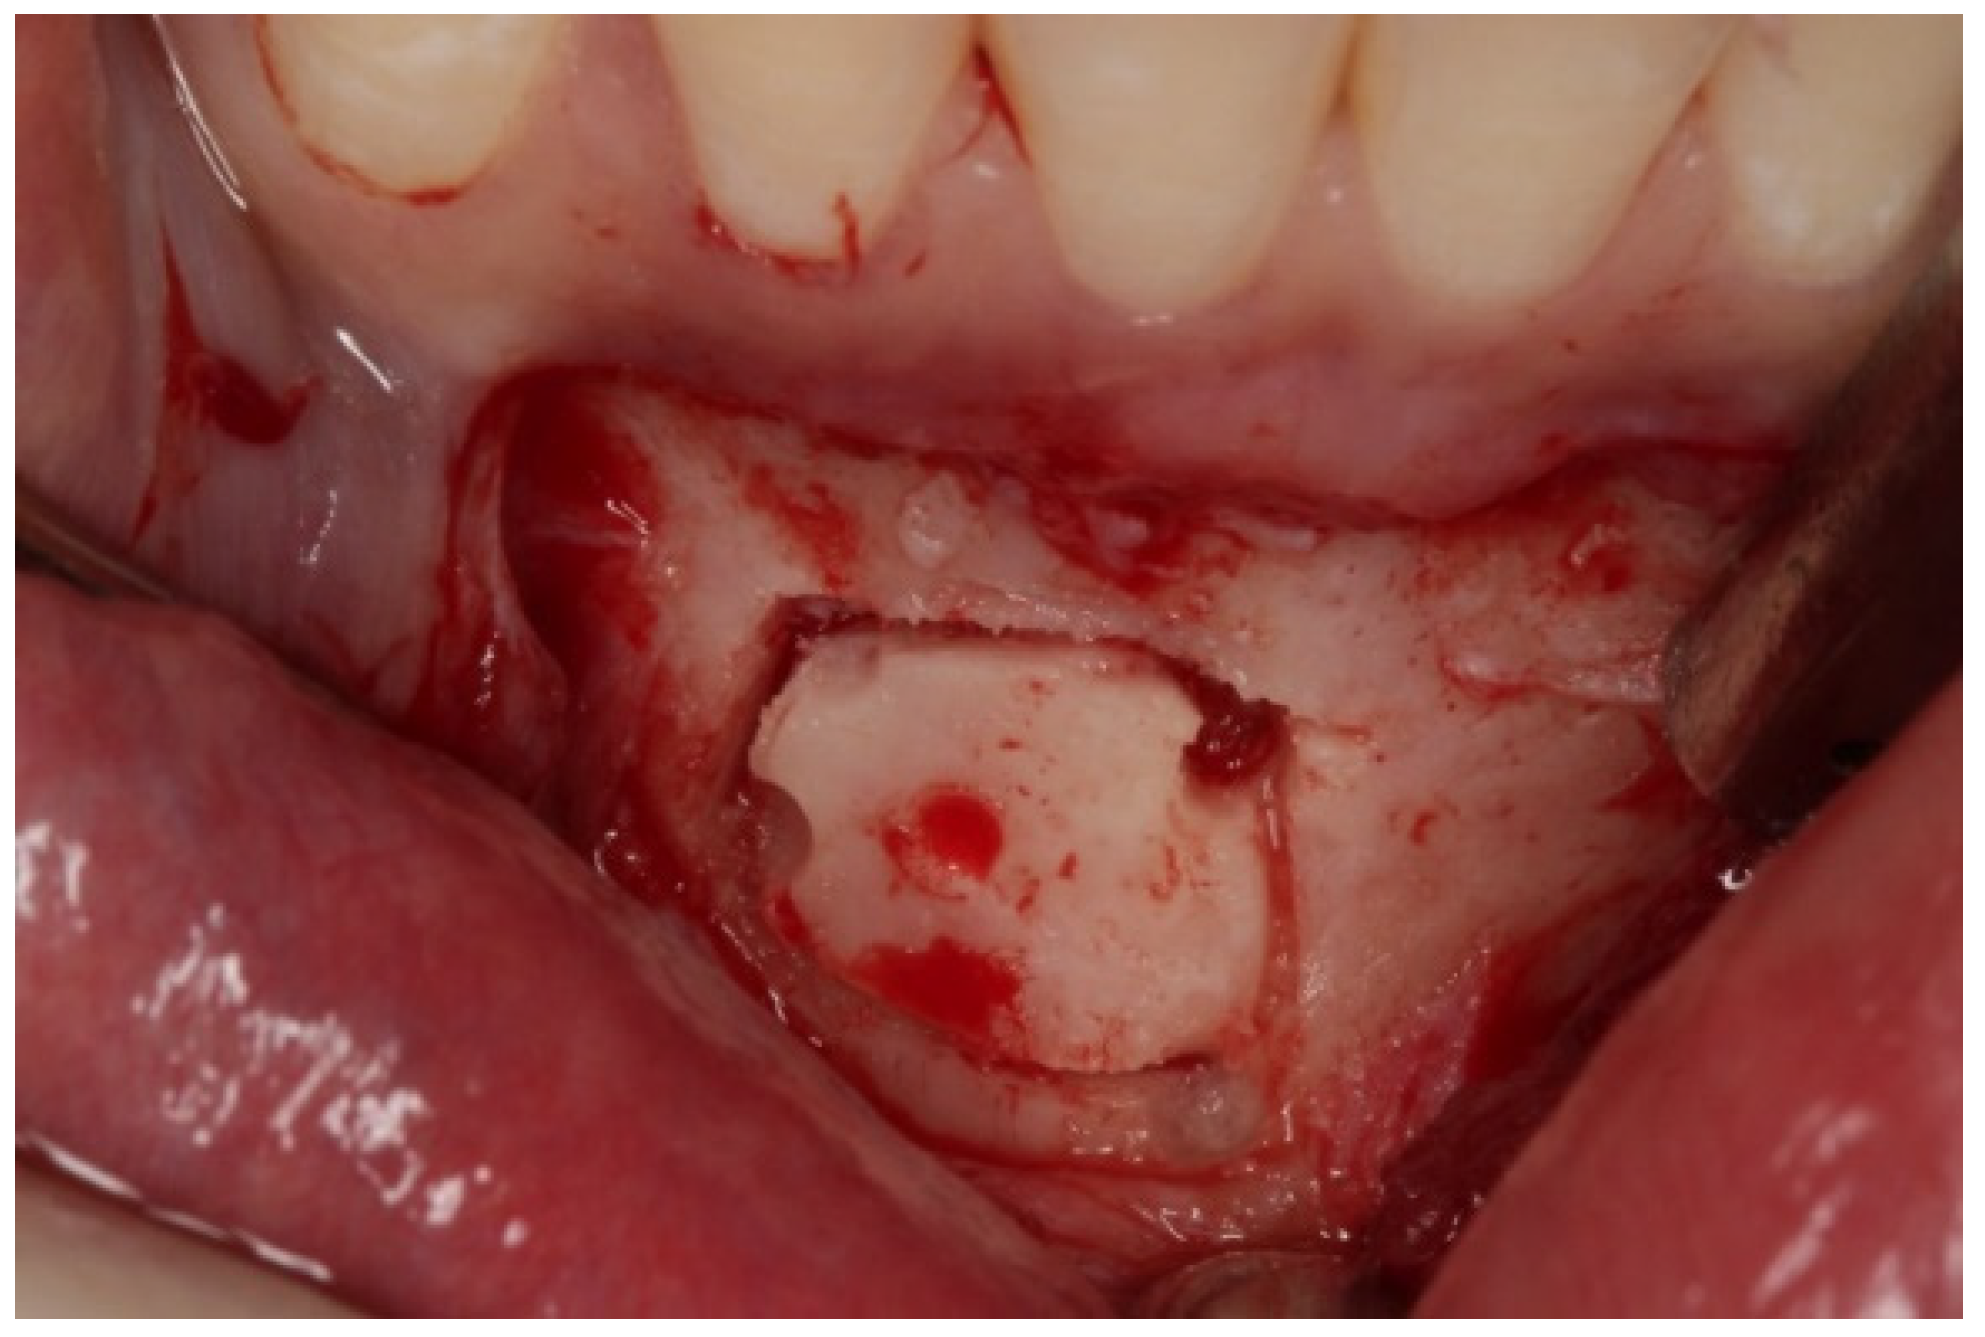

A double approach was used on the recipient jaw. On its vestibular aspect, compensating incisions were made distally on the lateral incisors (1.2 and 2.2), joined by an intrasulcular incision at the level of teeth 1.2 to 2.2, including a central incisor. A crestal incision was traced over the toothless residual ridge. A full-thickness trapezoidal flap was obtained upon curettage. On the palatal side, extensive curettage was performed to obtain a pocket covering the area from 1.2 to 2.2, thus exposing the bone defect and revealing the neurovascular bundle. The latter was next emptied with a bone scraper, and a 20 mm wide × 10 mm high cortico-cancellous block was obtained and placed palatally, covering the incisor foramen to increase the vestibulo–palatal width of the residual ridge. The blocks were held in position by titanium fixation micro-screws (BoneScrew kit® BioHorizons, Birmingham AL, USA) (Figure 4).

Figure 4.

Recipient area (A). Location of the bone block at the level of the foramen incisive (B) and on its incisal aspect (C). (D,E) Block fixation using fixing screws.